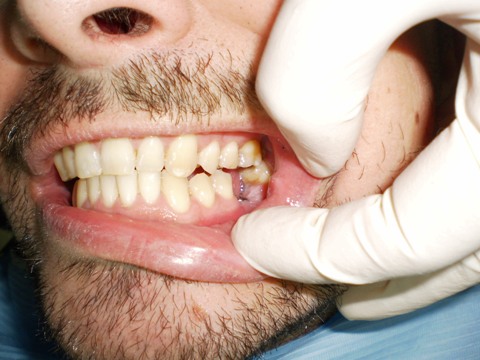

Ejemplo Implantes